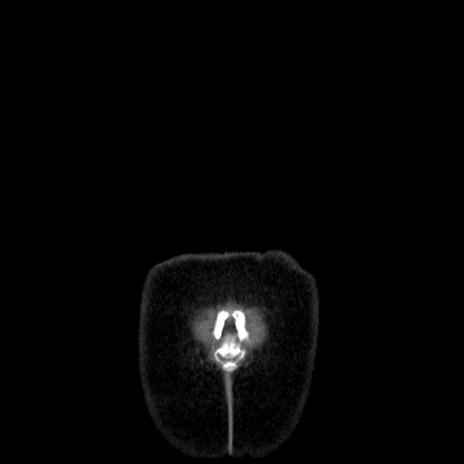

横断像